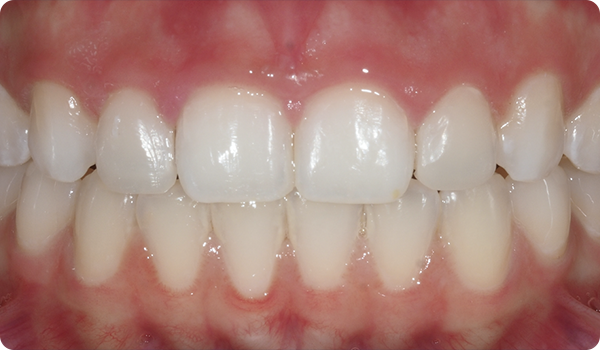

Smil på plads

Med Right får dine patienter det smil, de ønsker, inden for den ønskede tid, på en komfortabel og "usynlig" måde.

At justere tænder med Right er den perfekte og mest skånsomme forberedelse til fremtidig tandblegning eller facadebehandlinger, der vil perfektionere patientens smil.